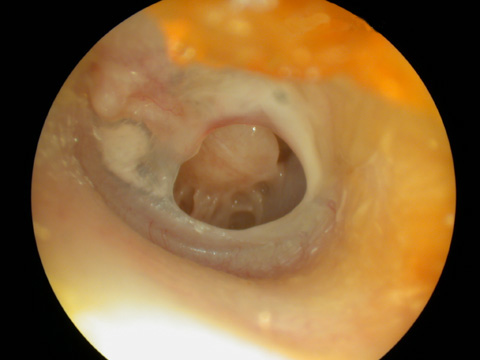

لوله تهویه در گوش میانی

گوش میانی با عوارض ناشی از عدم درمان مناسب و بموقع.

تصویر نشان میدهد ، گوش دچار پارگی پرده و چسبندگی استخوانچه های گوش میانی است.